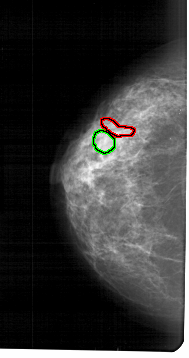

A_1470_1.LEFT_MLO

LEFT_MLO LINES 5491 PIXELS_PER_LINE 2926 BITS_PER_PIXEL 12 RESOLUTION 43.5 OVERLAY

FILE: A_1470_1.LEFT_MLO.OVERLAY

TOTAL_ABNORMALITIES 2

ABNORMALITY 1

LESION_TYPE MASS SHAPE LOBULATED MARGINS CIRCUMSCRIBED

ASSESSMENT 3

SUBTLETY 3

PATHOLOGY BENIGN

TOTAL_OUTLINES 1

BOUNDARY

ABNORMALITY 2

LESION_TYPE CALCIFICATION TYPE PLEOMORPHIC DISTRIBUTION CLUSTERED

ASSESSMENT 4

SUBTLETY 1

PATHOLOGY MALIGNANT